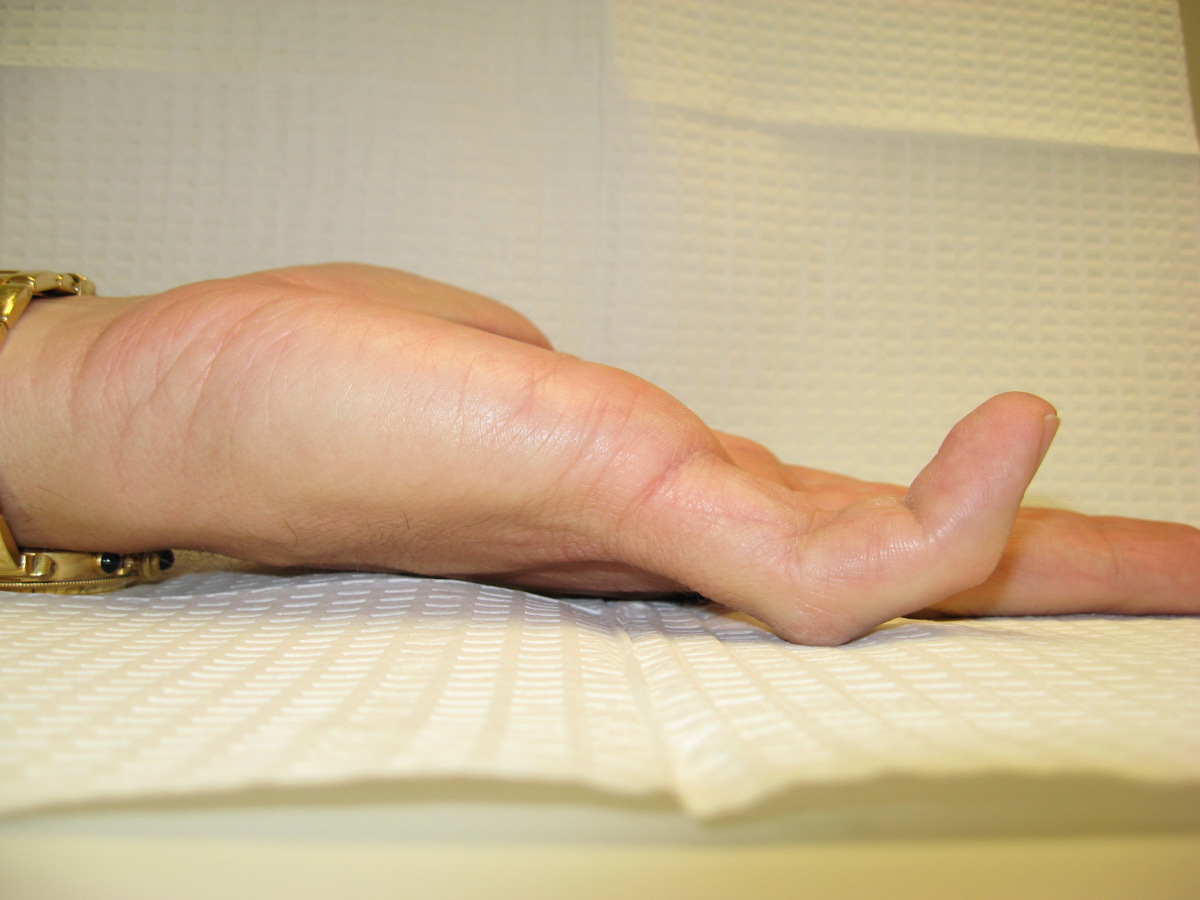

Case 4.

57 year old right handed man with a 22 year

history of Dupuytren disease affecting his

left small finger.